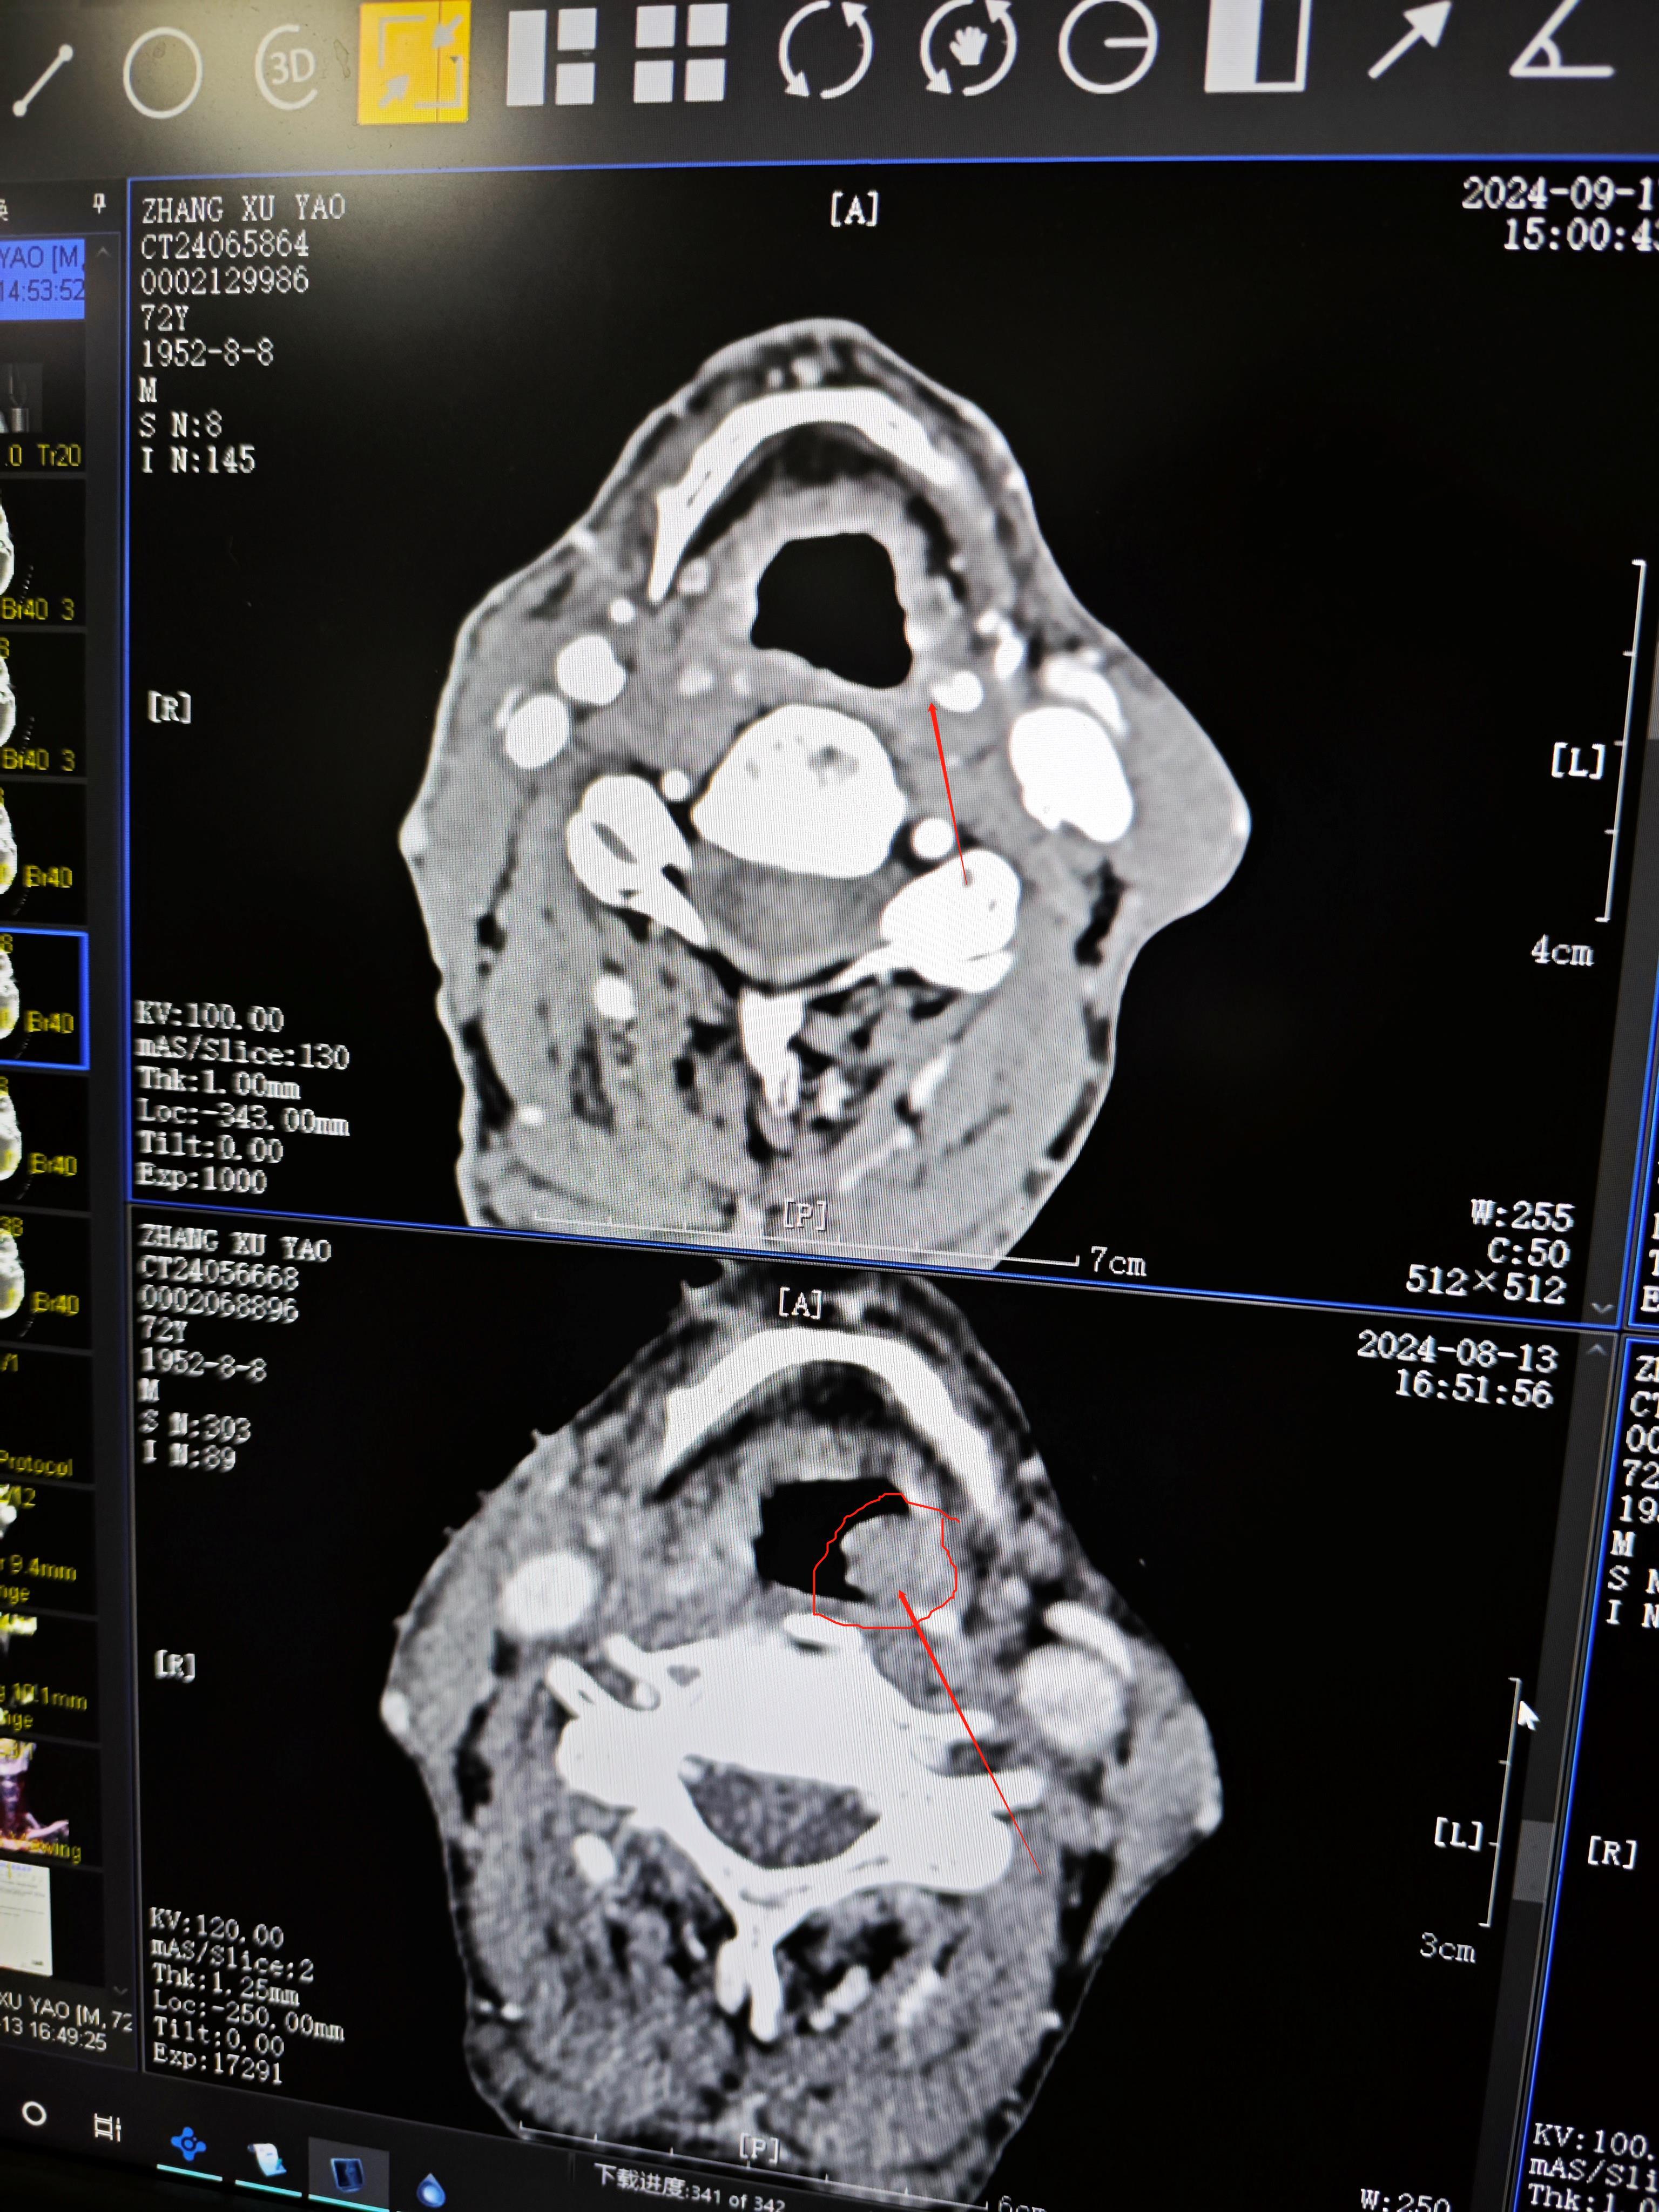

下咽癌以局部治疗为先导的综合治疗

图片尺寸3072x4098

图片尺寸3072x4096